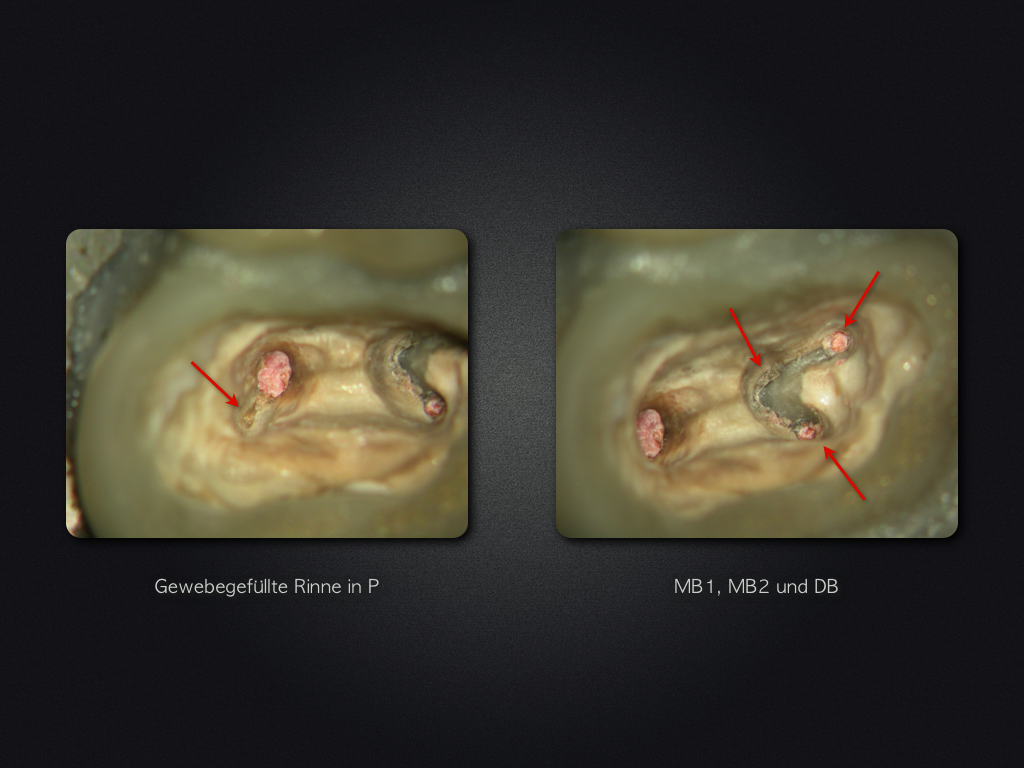

27D.005

Absolute Trockenlegung …